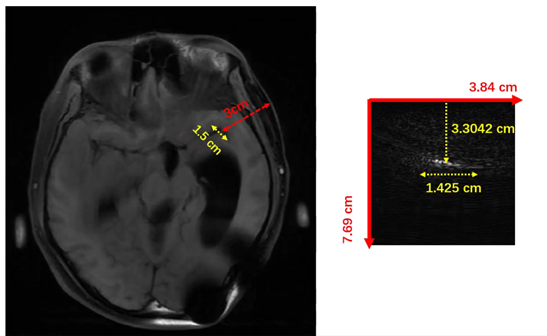

Figure 3: Comparison of MRI and PA Cerebral Artery Depths.

3.3 Registration with MRI

In addition, we further validated that the signals acquired by PAI originated from the MCA by matching them with MRI-derived anatomical features. As shown in Fig. 3, we first performed quantitative measurements of key geometric parameters of the MCA—namely, its depth and width—based on the MRI data.

Refer to caption

Figure 4: Registration of MRI and PA Cerebral Arteries.

Subsequently, the same parameter extraction strategy was applied to the PA images to obtain the depth and width of the MCA. A comparison between the two datasets revealed a high degree of consistency in both spatial scale and morphological characteristics. As shown in Fig. 4, the segmented vessel regions from PAI closely correspond to the MCA identified in the registered MRI images, indicating strong agreement between the two modalities.